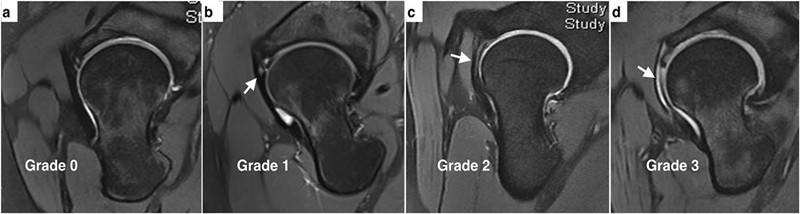

除厚度测量之外,也借助半月板的信号分级对前关节囊进行了内部信号分级。临床分为0~4级,‌正常表现是0级,出现点状信号为1级,出现线状信号为2级,出现断裂或者明显的贯通样分层为3级。‌‌